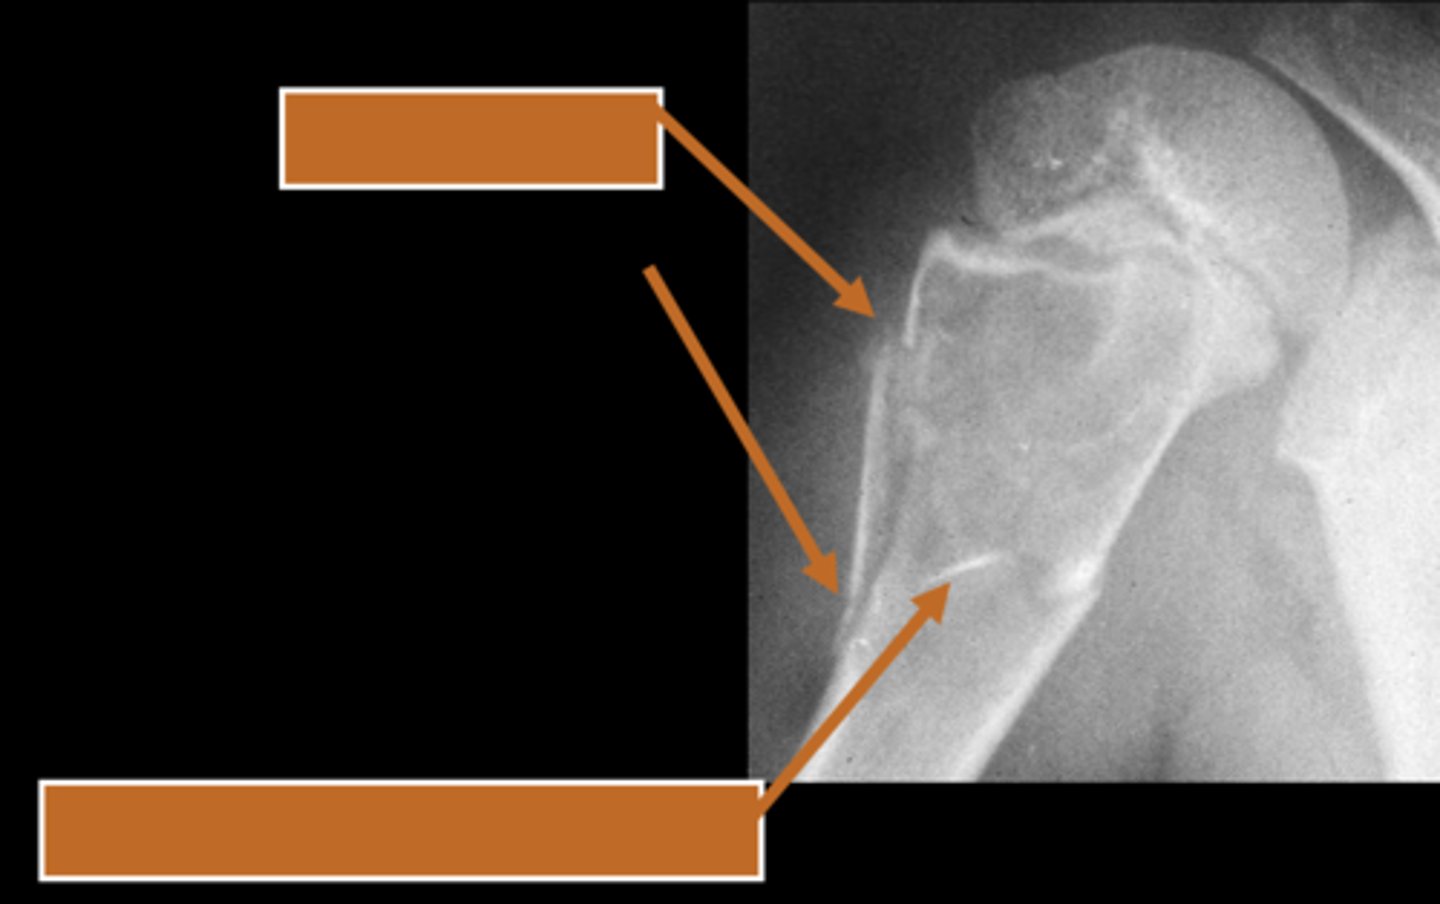

Pathologic fracture

ID radiographic feature of simple bone cyst indicated by the top arrow

<p>ID radiographic feature of simple bone cyst indicated by the top arrow</p>

Fallen fragment sign

ID radiographic feature of simple bone cyst indicated by the bottom arrow

<p>ID radiographic feature of simple bone cyst indicated by the bottom arrow</p>

Fallen fragment sign (10%)

- Cortex broke off

- Pathognomonic

<p>- Cortex broke off</p><p>- Pathognomonic</p>